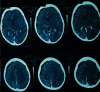

Sturge-Weber syndrome is a rare congenital neurocutaneous disorder characterized by dermatological, ophthalmological, and neurological manifestations. It occurs due to abnormal persistence of embryonic vascular plexus. Here, we describe a case of four years seven months female with seizures, developmental delay, intellectual disability, and bilateral port-wine stain diagnosed as type I (classical) Sturge-Weber syndrome. The ophthalmological evaluation was unremarkable. Electroencephalogram showed abnormalities suggestive of a structural lesion in the right cerebral hemisphere. CT scan of the head revealed volume loss of right brain parenchyma with linear, cortical, as well as subcortical calcifications more evident in the right hemisphere. The child should be followed up regularly until adulthood for ophthalmological evaluation, recurrence of seizures, and other manifestations of this disorder.